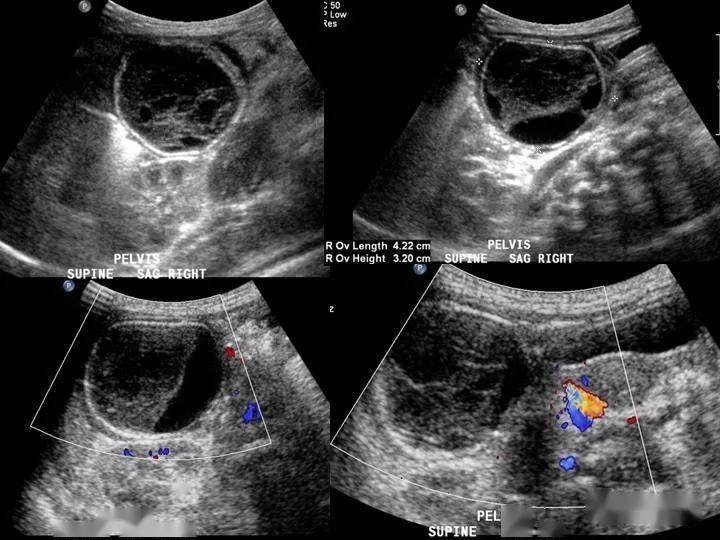

- 超声检查